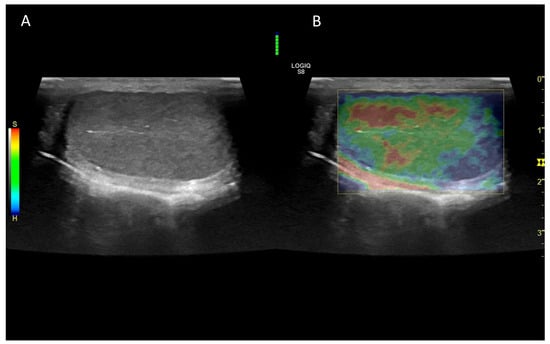

7. Ultrasound Elastography

7.1. Technology and Applications

7.2. Normal Findings

7.3. Abnormal Findings